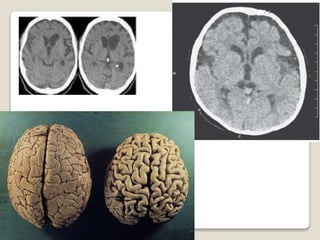

 SISTEMA NERVIOSO CENTRAL

 SISTEMA NERVIOSO – OFTALMOLOGICOS